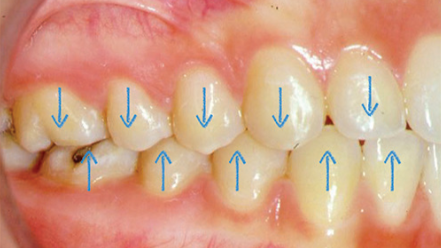

Patient Profile:

- 52-year-old male executive with history of nocturnal bruxism

- Presenting with generalized tooth wear (grade 3-4)

- Multiple failing posterior restorations

- Complaints of morning headaches and masticatory muscle fatigue

Diagnostic Findings:

- Sleep study confirmed moderate sleep bruxism (Bruxism Episode Index: 4.7)

- Surface EMG showed elevated masseter activity during rest periods

- Wear facets corresponded to eccentric grinding patterns

- Radiographic evidence of widened periodontal ligament spaces